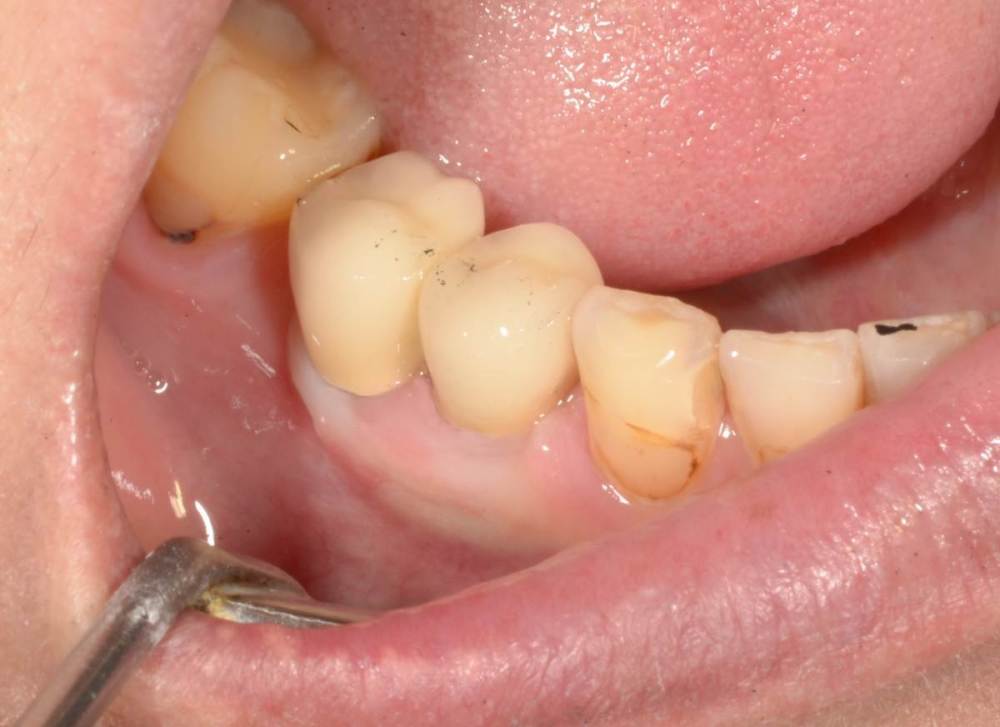

Большой Зеленый Опубликовано 27 мая, 2022 Поделиться Опубликовано 27 мая, 2022 Через 9 лет. Есть немного рецессии.. 2 Ссылка на комментарий

pit Опубликовано 27 мая, 2022 Поделиться Опубликовано 27 мая, 2022 4 часа назад, Большой Зеленый сказал: Через 9 лет. Есть немного рецессии.. Это связано исключительно с вестибулярной позицией импланта. Это как раз к вопросу про те минимальные 2мм до вестиболярной стенки, вне зависимости есть она или ты ее создаешь. Ссылка на комментарий

Женька Опубликовано 27 мая, 2022 Поделиться Опубликовано 27 мая, 2022 @Большой Зеленый это вроде ваш старый кейс? напомните пожалуйста, тут присыпка+мембранинг вестибулярно и вестибулярным лоскутом слегка послабленным всё закрыли? Ссылка на комментарий

Большой Зеленый Опубликовано 28 мая, 2022 Поделиться Опубликовано 28 мая, 2022 12 часов назад, Женька сказал: @Большой Зеленый это вроде ваш старый кейс? напомните пожалуйста, тут присыпка+мембранинг вестибулярно и вестибулярным лоскутом слегка послабленным всё закрыли? Да все так и есть как Вы и описали. Работе почти 10 лет. Присыпка мп3 от остеобила сверху "ильгамовская" губка . Считаю что результат вполне удовлетворительный. Рецессия обусловлена как уже сказали выше вестибулярным положением импланта ,ну и недозаглублен чуток. Ссылка на комментарий